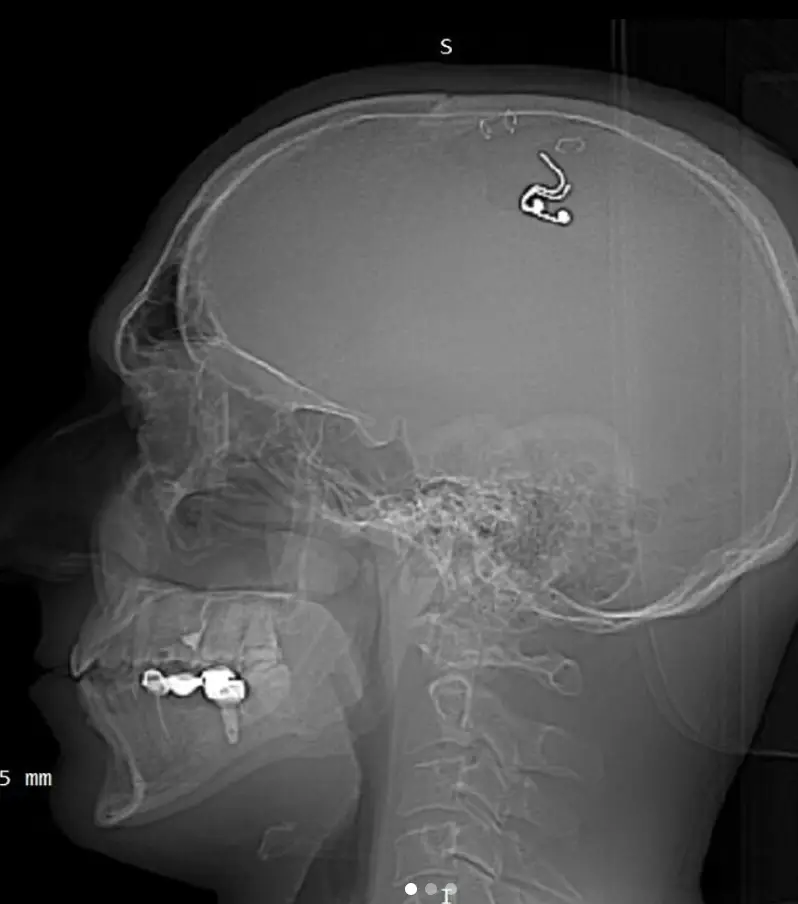

Despite opting to operate on his own brain, Raduga told the Daily Mail he has no neurosurgery qualifications and that he held parts of his skin back with paper clips while going at his skull with a drill he found in a hardware store so he can implant the electrode.

Five weeks after implanting the chip, Raduga removed it but there are concerns that he could already be at risk of long-lasting damage due to carrying out the procedure.